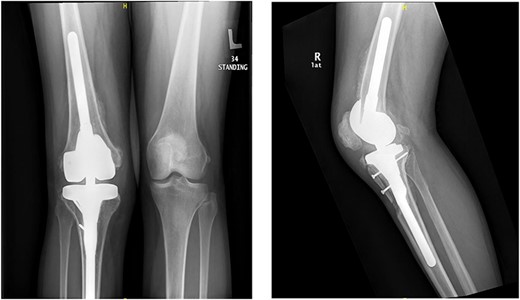

The patient lost some of her range of motion (ROM) in the post-operative period even with extensive physiotherapy. On her 4-month follow up appointment; ROM was 10–80°, which she sustained afterward. Plain radiographs continued to show no new HO formation at 4 months (Fig. 5).

Intraoperative image intensifier demonstrated position of the implant, screw and the osteotomy site.

Knee X-rays at 4 months visit continued to show no new HO formation, and continuation of healing of the osteotomy.